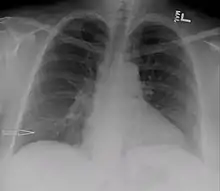

| Bilateral pleural effusions caused by urinothorax. | |